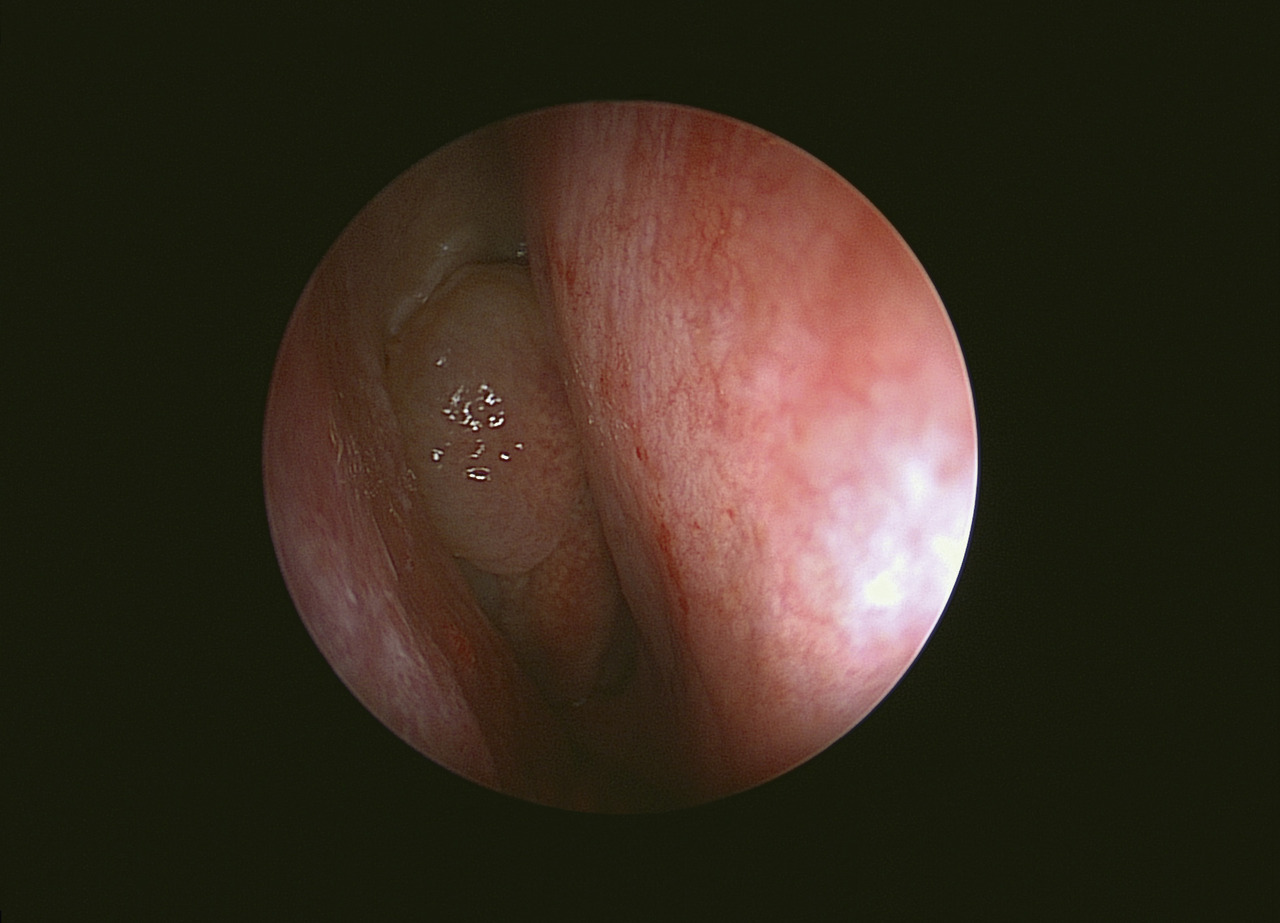

L’examen clinique nécessite l’emploi d’un fibroscope souple ; il ne peut donc être réalisé que par un oto-rhino-laryngologiste (ORL). Réalisé en consultation, il permet de voir la polypose (fig. 1 ) et d’en préciser la topographie (bilatérale et à peu près symétrique). Le volume de la polypose est évalué en trois stades :

– stade 1, les polypes occupent au maximum le tiers supérieur de la cavité nasale ;

– stade 2, les polypes occupent au maximum les deux tiers de la cavité nasale ;

– stade 3, les polypes occupent plus des deux tiers de la cavité nasale.

L’examen clinique de la cavité nasale recherche également des anomalies anatomiques (déviation septale, concha bullosa, ou séquelles d’interventions antérieures).